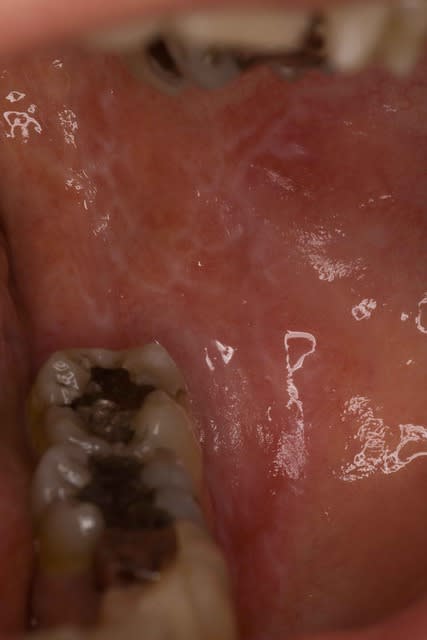

Pour moi ce truc a typiquement la gueule d'un lichen plan gingival erosif. Cherche d 'autres localisations pour confirmer (fond du vestibule posterieur, langue, reseau blanchatre. cf photo..)

Si c'est pas paro ( facile a verifier) c'est un lichen plan.

Un pemphigus vulgaire n'a pas du tout cet aspect et ce n'est pas la localisation , une pemphigoide non plus ( levre, grosse bulles etc....) Par ailleurs si c'est une maladie bulleuse et je ne vois que de l'erosion bizare...